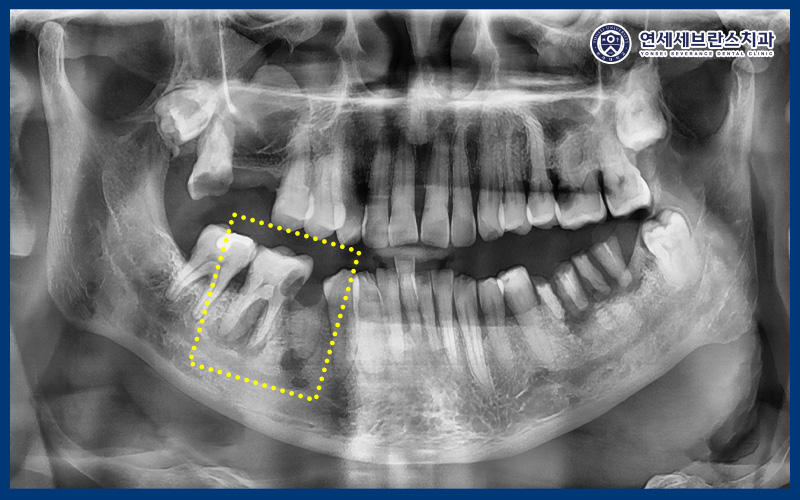

24.08.05

확인해 보니,

오른쪽 아래 통증을 느끼는 부위의

뿌리 끝 염증이 진행되어 있었는데요.

이로 인해 잇몸이 붓고

심한 압통이 동반되었으며,

일상적인 식사나 저작 시에도

큰 불편을 겪고 계셨는데요.

이러한 상태는 염증이

내부에 고여 있는 경우가 많아

자연적으로 호전되기 어렵고,

적절한 처치를 통해 염증을 배출하고

원인을 제거하는 과정이 필요합니다.

또한 다른 부위들도 치아가 부러지거나

충치가 생겨 치료가 필요한 부위가 많았습니다.

어금니가 대부분 소실된 상태로,

식사를 위한 저작 기능 회복을 위해서는

임플란트 치료가 필요한 상황이었습니다.

하지만 무엇보다 우선되어야 할 것은

환자분께서 호소하신 극심한 통증을

빠르게 완화시키는 것이었는데요.

CT를 촬영하여 확인해 보았을 때,

뿌리 끝 염증이 이미 신경까지 퍼져있었으며

조금만 더 늦었으면 치아 염증이

아래턱, 얼굴 감각까지 영향을 미칠 수 있는 상황이었으며

당장 임플란트 보다는 염증 제거 및

발치 후 치유 양상 확인이 필요했습니다.